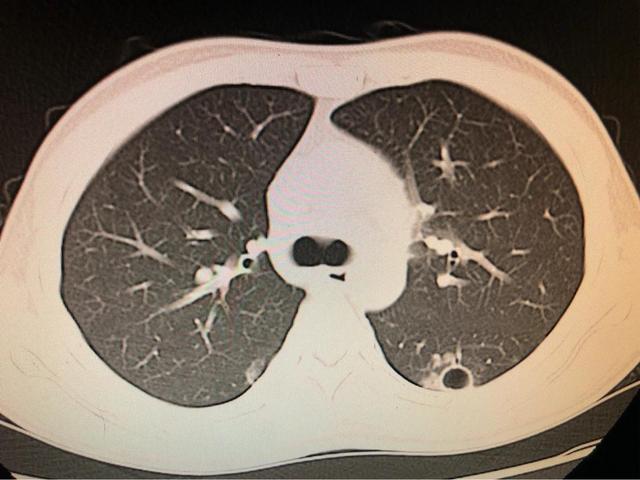

La tuberculose est une maladie infectieuse chronique causée par l'infection à Mycobacterium tuberculosis. La bactérie de la tuberculose peut envahir divers organes dans tout le corps, mais principalement les poumons, ce qui est appelé tuberculose pulmonaire, et se transmet principalement par les voies respiratoires. On observe souvent des symptômes systémiques tels qu'une fièvre légère et de la fatigue, ainsi que des manifestations respiratoires telles que la toux et l'hémoptysie. En général, si la toux et les expectorations ne se rétablissent pas pendant plus de deux semaines, le diagnostic de tuberculose peut être posé en combinaison avec d'autres tests cliniques, d'imagerie ou de laboratoire.